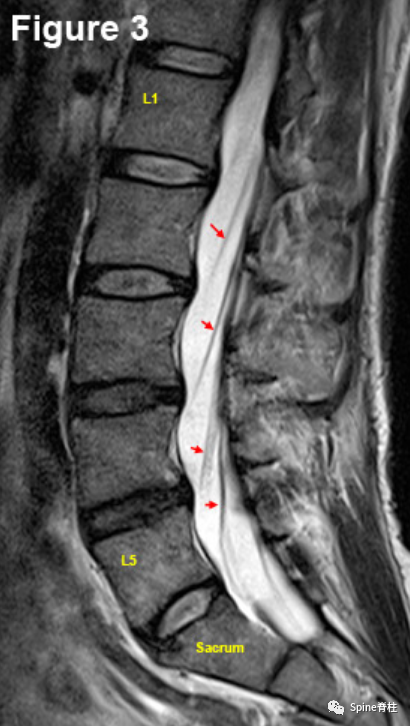

1. 腰椎MRI矢状面

腰椎MRI正中矢状面(mid-Sagittal Region)。可见两种主要的骨结构:方形椎体(黄色轮廓)和后弓的棘突(蓝色轮廓和S)。棘突与椎板的连接构成后弓的前边界,后弓也形成中央椎管的后部。这被黄韧带覆盖(绿色L)。椎体和后弓之间的极度高信号空间(几乎纯白色)是硬膜囊(红色T),充满着脑脊液。黑线为椎体后部(PB)、椎弓根和椎板之间的距离,为椎管的直径。在正中矢状面中,马尾神经根通常不太明显(淡蓝色箭头),除非它们靠近神经孔(未显示)。位于5个腰椎椎体之间的是5个腰椎间盘(红色轮廓和D),它们承载身体80%的轴向载荷。

腰椎MRI旁矢状位(Para-Sagittal Region),在硬膜囊内可见走行根(红色箭头),但L5除外,它已从硬膜囊出芽(第3个红箭头)

腰椎MRI旁矢状面(侧隐窝)可见L4-5椎间盘突出(红色箭头),接触到一个走行根,甚至将其推得有点偏离轨道(绿色箭头)